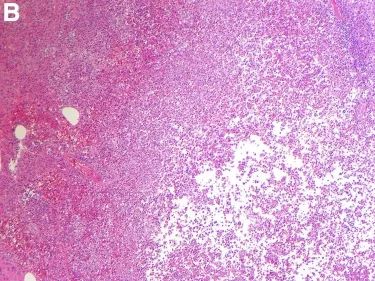

腹部CT检查发现阑尾增大且周围存在微量液体(图A),与急性阑尾炎表现一致。患者经阑尾切除术后症状缓解并经病理检查确诊(图B)。

(图B 病理检查)